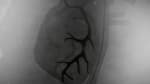

An angiogram is an X-ray test that uses dye and a camera to take pictures of the blood flow in an artery or a vein. An angiogram can be used to look at the arteries or veins in the head, arms, legs, chest, back, or belly. This test is done to look for problems in the arteries or veins.

When the catheter is in place, the dye is injected through it. You may be asked to take a breath and hold it for several seconds. Several X-ray pictures will be taken one after another. These will be available right away for your doctor to look at. You need to lie very still so the pictures are clear. More pictures may be taken.

Your doctor may tell you some results right after the test. Full results are usually ready the same day.

The blood vessels are normal in shape, size, location, and number.

The dye flows evenly through the blood vessels.

No narrowing, blockage, bulging, or other problem of the blood vessels is seen.